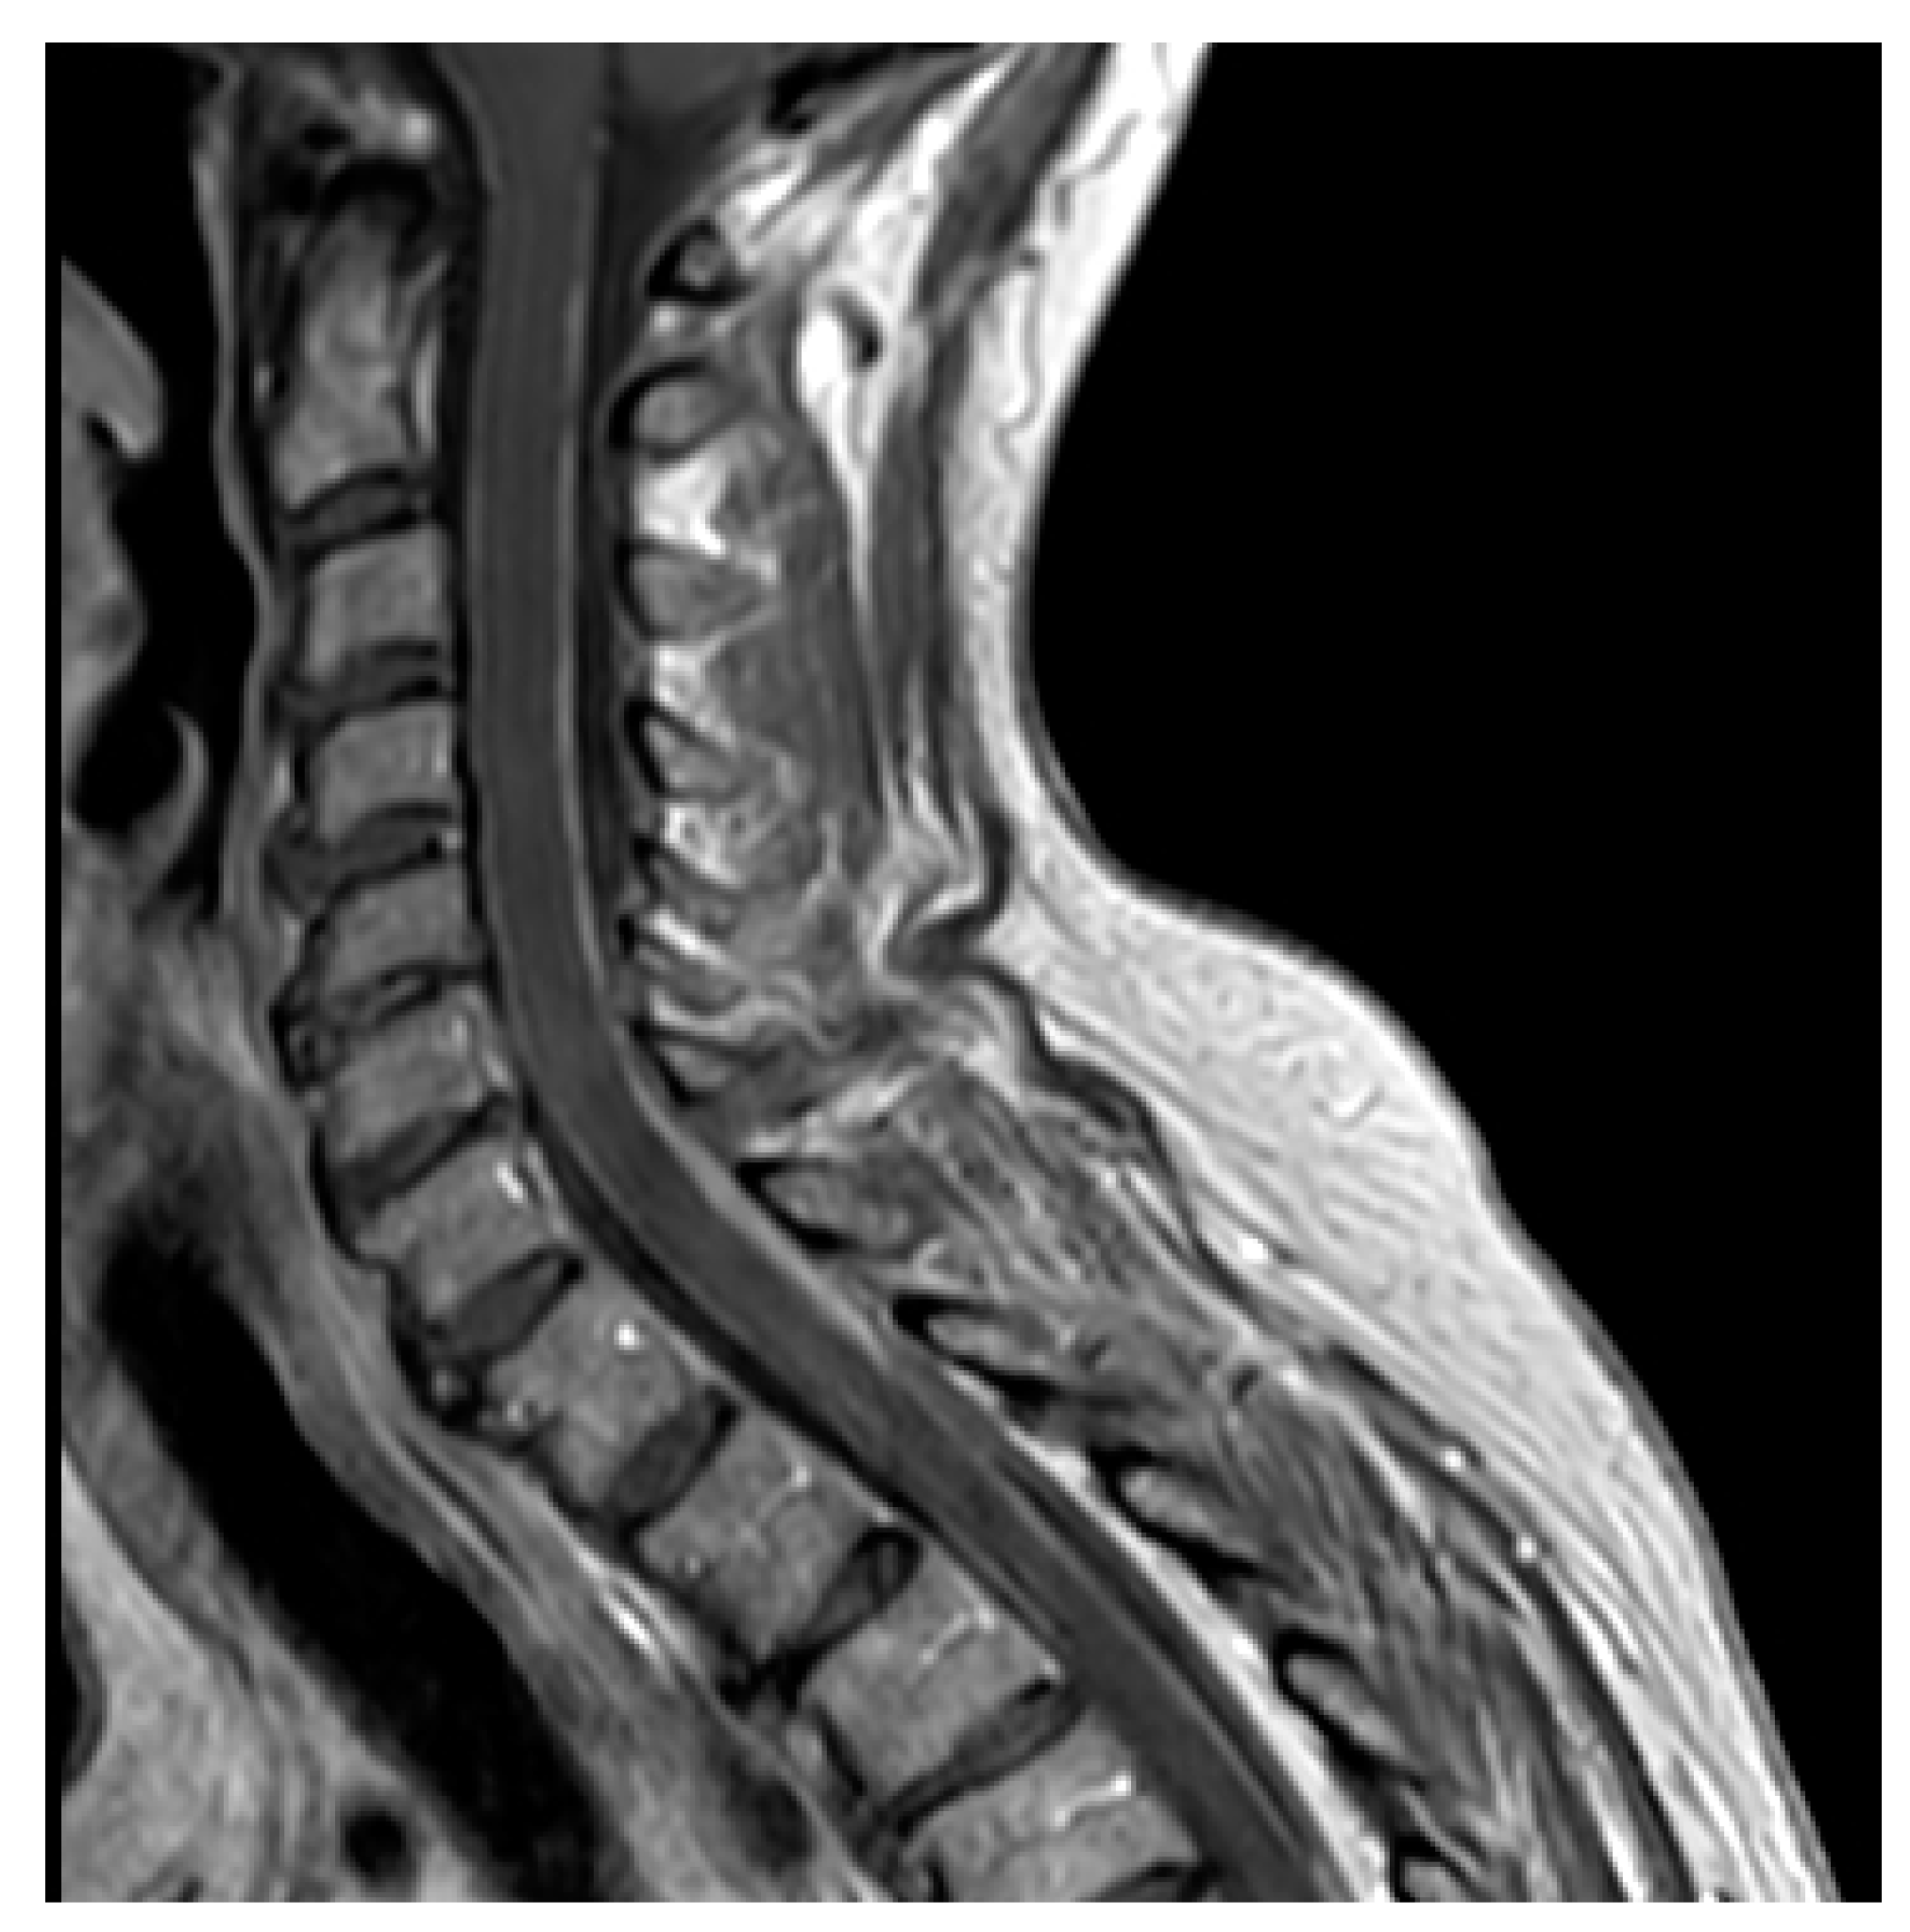

4.2. Neuroimaging Assessment